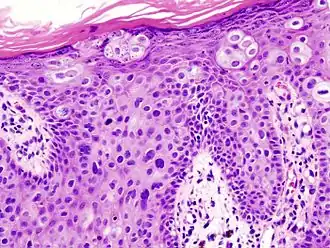

Histological characteristics

Histopathologically, the epidermis in cSCC in situ (Bowen's disease) will show hyperkeratosis and parakeratosis. There will also be marked acanthosis with elongation and thickening of the rete ridges. These changes will overly keratinocytic cells, which are often highly atypical and may have a more unusual appearance than invasive cSCC. The atypia spans the full thickness of the epidermis, with the keratinocytes demonstrating intense mitotic activity, pleomorphism, and greatly enlarged nuclei. They will also show a loss of maturity and polarity, giving the epidermis a disordered or "windblown" appearance.

Two types of multinucleated cells may be seen: the first will present as a multinucleated giant cell, and the second will appear as a dyskeratotic cell engulfed in the cytoplasm of a keratinocyte. Occasionally, cells of the upper epidermis will undergo vacuolization, demonstrating an abundant and strongly eosinophilic cytoplasm. There may be a mild to moderate lymphohistiocytic infiltrate detected in the upper dermis.[12]

Histopathology of squamous-cell carcinoma in situ (black arrow), compared to normal skin, showing marked atypia. -

Squamous-cell carcinoma in situ, showing prominent dyskeratosis and aberrant mitoses at all levels of the epidermis, along with marked parakeratosis.[12]